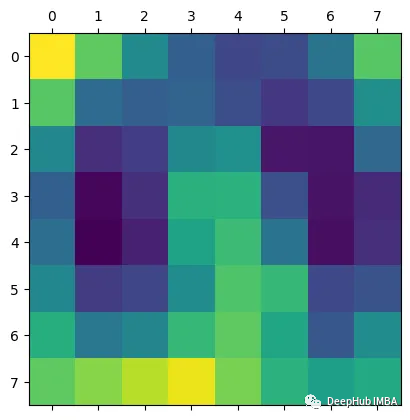

plt.matshow(heatmap.detach())

结果如下:

得到的激活包含1024个特征映射,这些特征映射捕获输入图像的不同方面,每个方面的空间分辨率为8x8。通过钩子获得的梯度表示每个特征映射对最终预测的重要性。通过计算梯度和激活的元素积可以获得突出显示图像最相关部分的特征映射的加权和。通过计算加权特征图的全局平均值,可以得到一个单一的热图,该热图表明图像中对模型预测最重要的区域。这就是Grad-CAM,它提供了模型决策过程的可视化解释,可以帮助我们解释和调试模型的行为。

但是这个图能代表什么呢?我们将他与图片进行整合就能更加清晰的可视化了。